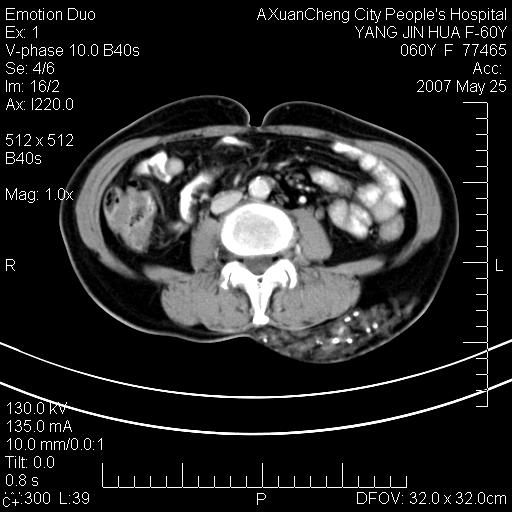

左背部皮下良性肿瘤,密度不均,边界不清,内有脂肪、钙化,增强扫描无明显强化,血管平滑肌脂肪瘤?进一步诊断有困难,建议穿刺活检。

左侧背部皮下混杂密度肿块,结构较疏松,边缘欠光整,内有多发斑点状钙化,考虑:皮下血管瘤。

左背部皮下良性肿瘤,密度不均,边界不清,内有脂肪、钙化,增强扫描无明显强化,血管平滑肌脂肪瘤?进一步诊断有困难,建议穿刺活检。还有,我想还是问一下病史,患者有外伤史吗?能否完全排除外伤后机化的....

血管平滑肌脂肪瘤,支持!另应详细了解病史,待除外骨化性肌炎。

完全支持穿刺..